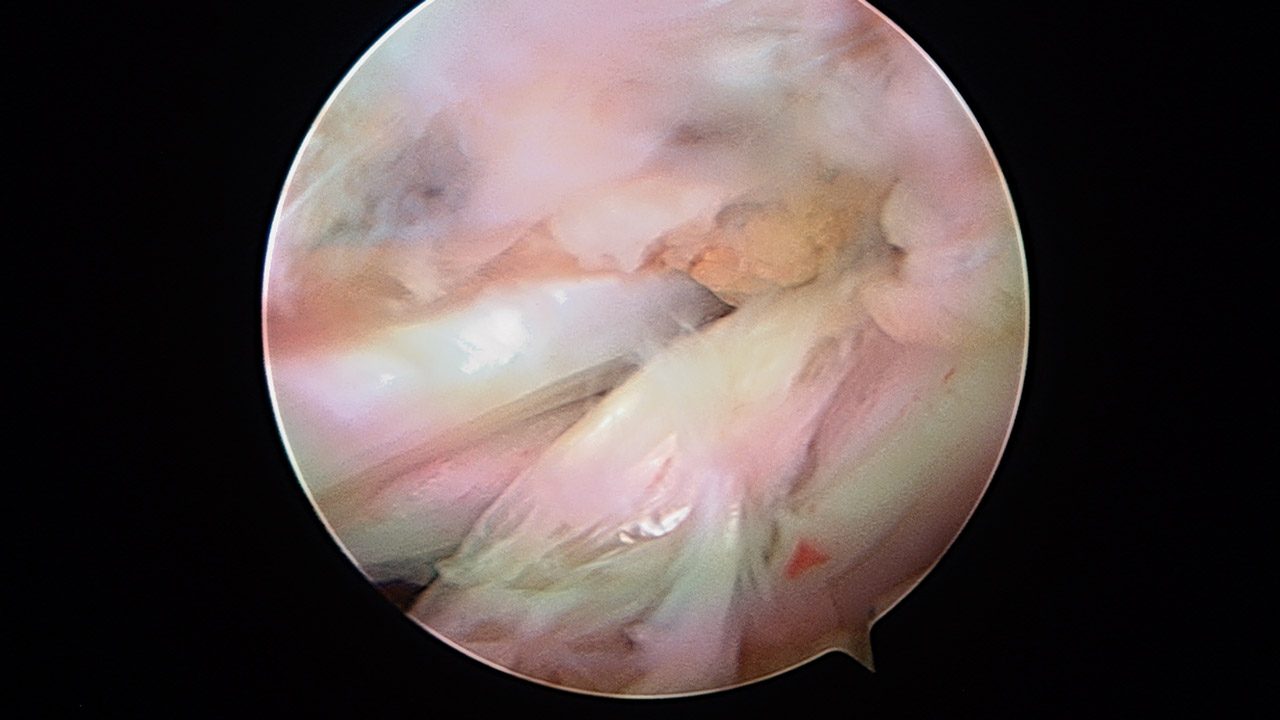

Presentamos una técnica quirúrgica artroscópica para los casos de inestabilidad traumática o atraumática de hombro, con hiperlaxitud multidireccional asociada, en los que hayan fracasado los tratamientos conservadores u otras técnicas quirúrgicas de plicatura capsular, y no presenten déficit óseo importante. Consiste en la plicatura del ligamento glenohumeral inferior (anteroinferior y posteroinferior) y la realización de una ligamentoplastia de refuerzo anterior artroscópica con aloinjerto en disposición transubescapular.

We present an arthroscopic surgical technique for cases of traumatic instability or atraumatic of the shoulder, with associated multidirectional hyperlaxity in which conservative treatments have failed, or other surgical techniques of plication capsular, and do not present major bone deficits. It consists of the plication of the lower glenohumeral ligament (anteroinferior and posteroinferior) and the accomplishment of an arthroscopic anterior reinforcement ligamentoplasty with allograft in a trans-scapular arrangement.